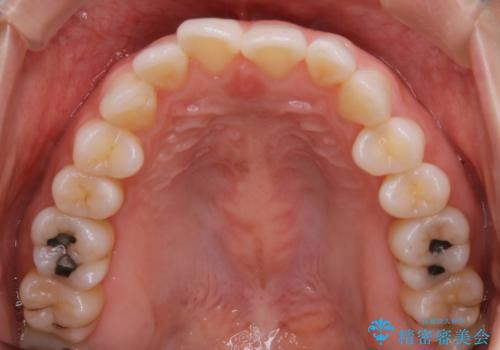

【非抜歯】前歯のガタつき マウスピースの部分矯正

- 上下の前歯の細かいガタつきの治療をご希望されて来院されました。

奥歯部分にはガタつきや噛み合わせの問題などがほとんど見られず、前歯のガタつきも軽度だったため、インビザライン ライト パッケージでの部分矯正を行うこととなりました。

今回のケースでは奥歯の噛み合わせに問題がほぼみられなかったため、前歯の位置のみに焦点を当て部分矯正を行いました。